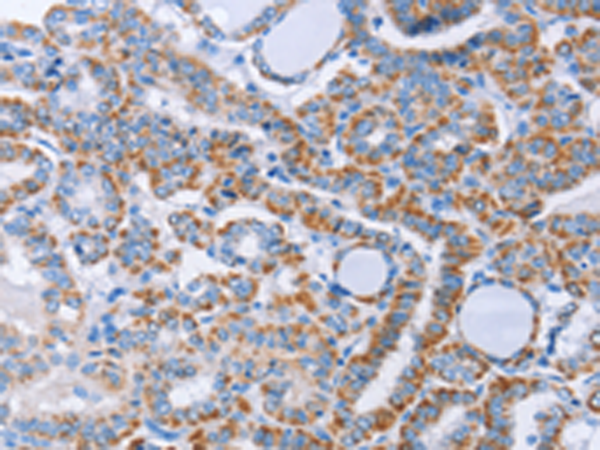

分类: 科研抗体货号: P07423别名: LRP, VAULT1应用: WB,IHC反应种属: Human, Mouse, Rat